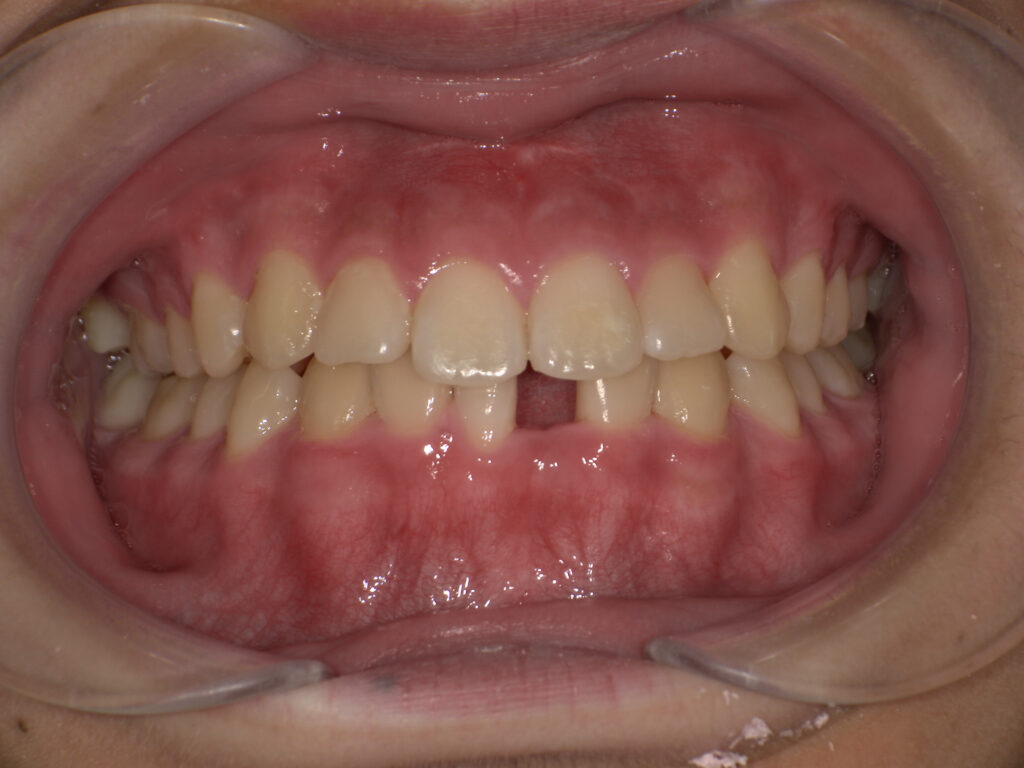

こどものすきっ歯(正中離開)

子どもの前歯にすき間があると、心配になる保護者の方も多いですが、乳歯期に歯と歯の間にすき間があるのは正常な成長過程です。これは、将来生えてくる永久歯のためのスペースを確保する大切な役割があります。永久歯は乳歯よりも大きいため、ある程度のすき間があった方が、きれいに並びやすいとされています。

また、前歯が永久歯に生え変わる時期には、「みにくいアヒルの子の時代」と呼ばれる歯並びの変化が見られることがあります。この時期は、前歯が少し外側に開いたり、すきっ歯のように見えることがありますが、犬歯(糸切り歯)が生えてくることで歯列が押され、自然にすき間が閉じていくことが多いです。ただし、次のような場合は歯科医院での相談をおすすめします。

・永久歯が生えそろってもすき間が閉じない

・上唇小帯(上唇と歯ぐきをつなぐ筋)が強く、前歯の間に入り込んでいる

・舌で歯を押す癖(舌癖)がある

歯並びの成長には個人差があるため、気になる場合は早めに歯科医院で確認してもらうと安心です。